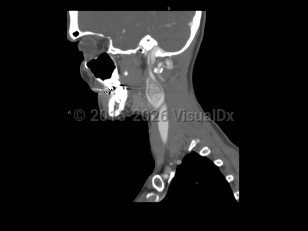

Peritonsillar abscessPeritonsillar abscess

Retropharyngeal abscess